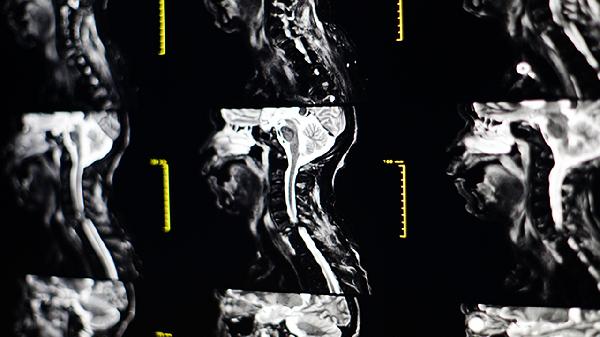

颈动脉斑块3.5*1.5严重吗

颈动脉斑块3.5*1.5属于较大斑块,可能增加中风风险,需及时采取干预措施。斑块的形成与血脂异常、高血压、糖尿病等因素相关,治疗包括药物治疗、生活方式调整及必要时手术干预。